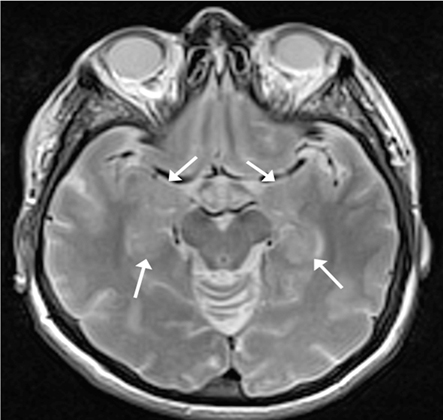

- MRI/CT brain:

hypodensities within brain parenchyma on CT and T1-weighted MRI; focal ischaemic infarcts and/or small vessel ischaemic disease with hyperintensities on T2-weighted MRI